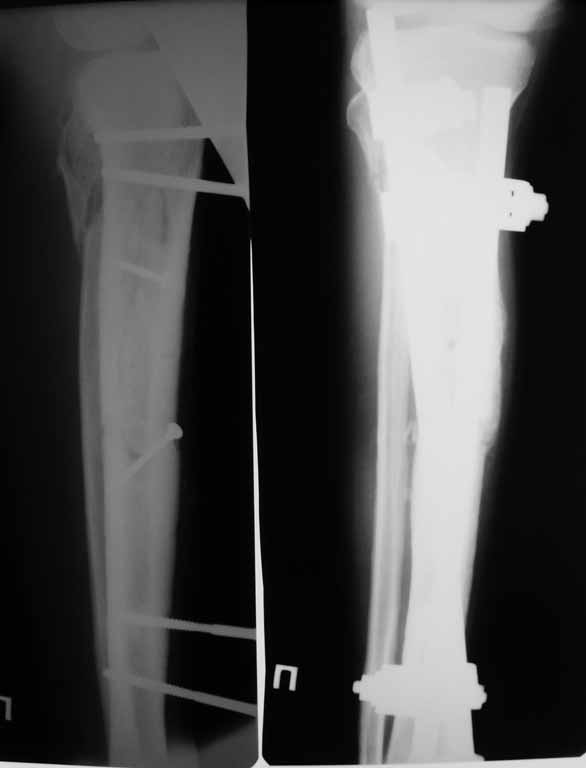

Привожу пример: Пациент с открытой тяжелой ЧМТ.

Диагноз при поступлении: Открытый оскольчатый перелом свода и основания черепа,субдуральная гематома, ушиб головного мозга тяжелой степени. Открытый оскольчатый перелом костей правой голени. Шок 3 Кома 3

При поступлении оперирован : трепанация, ПХО, остеосинтез голени.

Консолидация в аппарате внешней фиксации к 2 месяцам. Аппарат снят через 2,5 месяца.